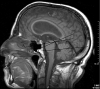

Background and purpose: Many theories of normal pressure hydrocephalus (NPH) stress the importance of ischemia in the deep white matter. Alternate theories stress a reduction in superficial venous compliance and changes in pulse-wave propagation. An overlap in the cerebral blood flow volumes measured between NPH and controls suggests that ischemia may not be a prerequisite for this condition. This study sought to compare blood flow and compliance measures in a cohort of patients with NPH selected for having arterial inflows above the normal range to see if deep brain ischemia or superficial hemodynamic changes contribute to the pathophysiology of NPH.

Materials and methods: Twenty patients with NPH and arterial inflows above the normal range were selected. They underwent MR imaging with flow quantification measuring the total blood inflow, sagittal/straight sinus outflow, aqueduct stroke volume, and arteriovenous delay (AVD). Patients were compared with 12 age-matched controls.

Results: The deep outflow volumes were normal. The superficial venous outflow was reduced as a percentage of the inflow by 9% (P = .04). The sagittal sinus compliance as measured by the AVD was reduced by 50% (P = .0001), and the aqueduct stroke volume was elevated by 192% (P = .02).

Conclusion: Ischemia in the deep venous territory is not a prerequisite for NPH. Patients with high-inflow NPH show alterations in superficial venous compliance and a reduction in the blood flow returning via the sagittal sinus. These changes together suggest that an elevation in superficial venous pressure may occur in NPH.